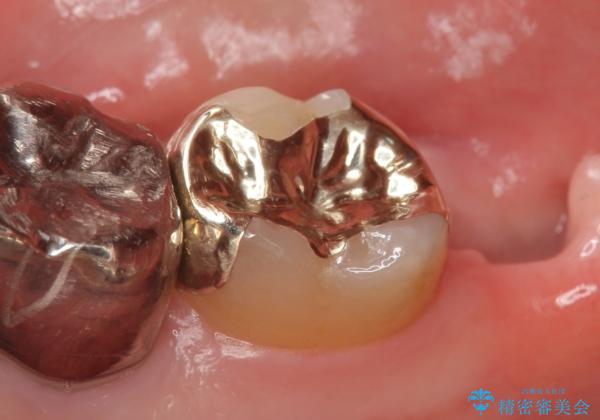

- 冷たいものを飲むと右下の奥歯が痛むので診て欲しいといらっしゃった方の症例です。

銀歯及び虫歯を除去後、より適合の良いPGA(ゴールド)インレーによる修復を行いました。

ゴールドは化学的な安定性が高いため変色や腐食がほとんどなく、アレルギーなども起こりにくい人体に優しい素材です。

また硬さも天然歯に近いため周囲の歯への影響も少なく、さらに適合もよいため虫歯の再発も少ない、とても補綴に適した材料です。